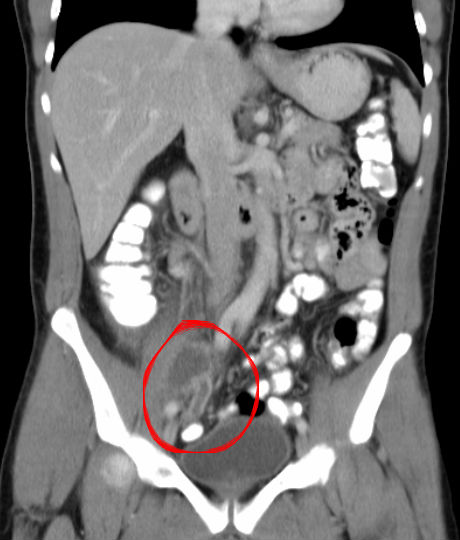

Tanda-tanda apendiks pada kanak-kanak adalah berbeza dari gejala apendiks di kalangan orang dewasa. Pada saat ini anak perempuan harus memakai pembalut untuk membantu menampung darah yang keluar. Pemeriksaan Tanda obturator Pasien ditidurkan dengan polisi terlentang kemudian angkat kaki kanan dengan tungkai dan paha membentuk 90 derajat kemudian dorong lutut kanan ke arah perut jika seseorang merasa nyeri pada perut bagian bawah maka dapat disimpulkan bahwa ia mengalami peradangan pada daerah apendiks.

Ultrasound abdomen atau imbasan CT untuk melihat apakah apendiks meradang. Apakah rawatan Apendiks yang diberikan oleh pihak doktor. Penyebab Gejala Komplikasi dan Pengobatan.

Sakit pada abdomen diikuti bengkak pada bahagian bawah kanan perut. Tanda-tanda awal apendisitis akut bisa kerep diganggu. Tanda-tanda dan gejala apendiks biasanya dinyatakan gejala sakit sangat kuat.